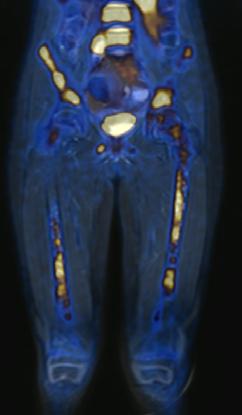

El neuroblastoma es la neoplasia sólida extracraneal más frecuente en niños. Al momento del diagnóstico, el 50% de los pacientes presentan enfermedad metastásica. Estos pacientes tienen un alto riesgo de enfermedad refractaria o recurrente y un pronóstico adverso. Durante las últimas décadas, la medicina nuclear ha sido fundamental para la estadificación y la evaluación de la respuesta al tratamiento del neuroblastoma. Actualmente, la técnica de imagen nuclear estándar es la gammagrafía corporal total con meta-[ 131I ]yodobencilguanidina ([ 131I ]mIBG) en México, generalmente combinada con tomografía computarizada por emisión monofotónica con tomografía computarizada (SPECT-CT). Sin embargo, el 10% de los neuroblastomas no son ávidos por este radiofármaco y las imágenes con [131I]mIBG tienen una resolución espacial relativamente baja, lo que resulta en una sensibilidad limitada para lesiones más pequeñas, además de conferir mayor dosis de radiación al paciente. Se necesitan métodos más precisos para evaluar la extensión total del neuroblastoma debido a su comportamiento y variabilidad tumoral heterogénea con el fin de optimizar las estrategias de tratamiento. La imagen híbrida ha llevado a la introducción de radiotrazadores compatibles con la tomografía por emisión de positrones (PET) en neuroblastomas, como [ 124 I]mIBG, [18F]mFBG, [18 F]FDG, [ 18F]Octreotide, 6[18F]F-DOPA y [11 C]mHED. La metodología PET ofrece mayores y múltiples ventajas sobre la SPECT, incluida una resolución superior y un rango tomográfico de cuerpo entero, además del beneficio de la información en las diversas secuencias al combinarlo con la resonancia magnética.

Femenino de 7 años con diagnóstico de Neuroblastoma, se realiza PET/RM con [18F]F-DOPA para estadiaje, con evidencia de lesión primaria a nivel de retroperitoneo y conglomerados locoregionales así como infiltración a médula ósea del esqueleto axial y apendicular (Figura 1A), posteriormente la paciente fue tratada quirúrgicamente con resección de la lesión primaria así como tratamiento con inmunoterapia y transplante autólogo de médula ósea además de radioterapia. Al presentar refractariedad al tratamiento comentado, se plantea la posibilidad de administrar Lutecio (177Lu) oxodotreotide, por lo que se sugiere realizar PET/RM con [18F]Octreotide para valorar expresión de receptores de somatostatina y considerar la terapia con radionúclidos para receptores de péptidos (PRRT), el estudio muestra evidencia de sobreexpresión anormal de dichos receptores en retroperitoneo, espacio subpleural izquierdo además de esqueleto axial y apendicular (Figura 1B).

Estudio PET con 6-[18F]DOPA 3A) y [18F]OCTREOTIDE 3B) en cortes coronales de secuencias T2 de miembros pélvicos y con imágenes fusionadas, donde se identifica mayor sobreexpresión anormal de los receptores de somatostatina al compararlos con 6-[18F]DOPA, y que hace candidata a la paciente para PRRT.